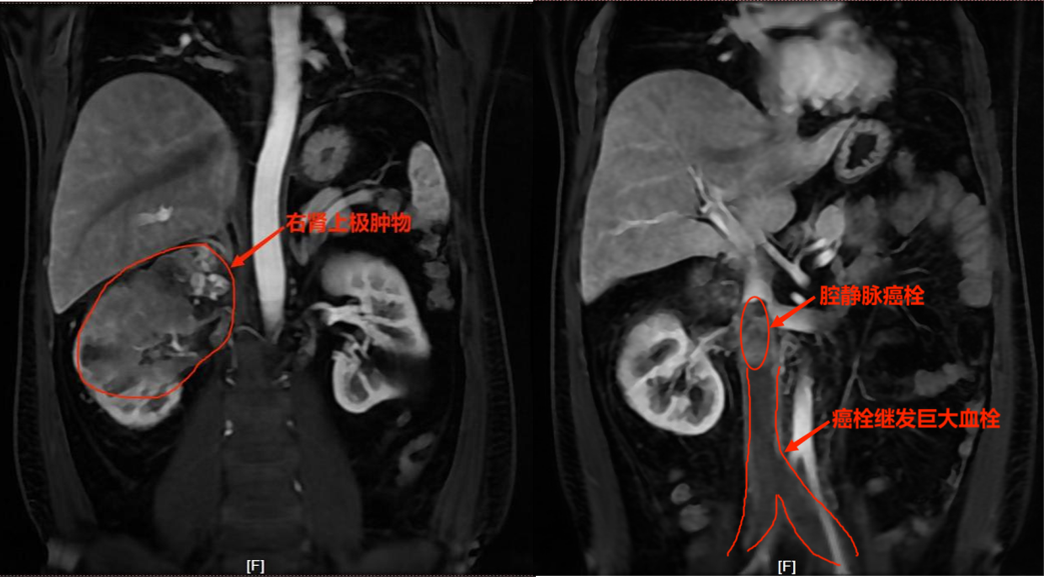

近日,45岁的张先生右侧突然感到腰痛不适并且下肢肿痛乏力,在家人陪伴下来我院就诊。经诊断检查确诊为右侧肾癌,入院进一步CTA检查提示:右肾占位;下腔静脉、左侧髂静脉及两侧肾静脉内栓子形成可能,双侧股静脉血栓形成可能。

肾癌合并下腔静脉癌栓手术相对复杂,手术风险巨大,一直以来被称为泌尿外科领域的“禁区”,手术中面临大出血、癌栓脱落导致肺栓塞可能;且张先生腔静脉瘤栓下方继发巨大血栓,一直延续至双侧股静脉上方,如手术取栓则风险更大。但是对于肾癌合并下腔静脉瘤栓的患者,肾根治性切除术及彻底切除瘤栓是目前最有效的治疗手段,患者术后5年生存率34%-64%;如果不手术,中位预期寿命约为5个月。